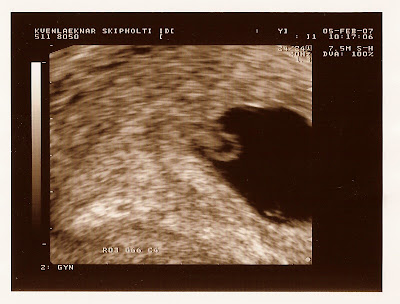

Á efstu myndinni er súkkulaðibaunin bara 3 mm hehe... og sést ekkert eila, bara fósturpokinn. Ég á eftir að skanna inn nýjustu myndirnar, þær eru kúl sko. Annars er baunin í stuði og mjög mikill fimleikagarpur. Henni heilsast vel en gjörir móður sinni lífið leitt!

Já þetta er klárlega þrjósk súkkulaðibaun. Hún ætlar greinilega ekki að fara fet, allavega ekki strax. Ég hlakka til að hitta hana. Á neðstu myndinni, það er hringur vinstra megin við skvísuna. Hvað er það?

Þetta er svo kallaður nestispoki. Held að það færi næring þarna í gegn handa fóstrinu. Ég ældi sem betur fer ekki mjög mikið en var stöðugt óglatt og ég er komin með bumbu!! ;)